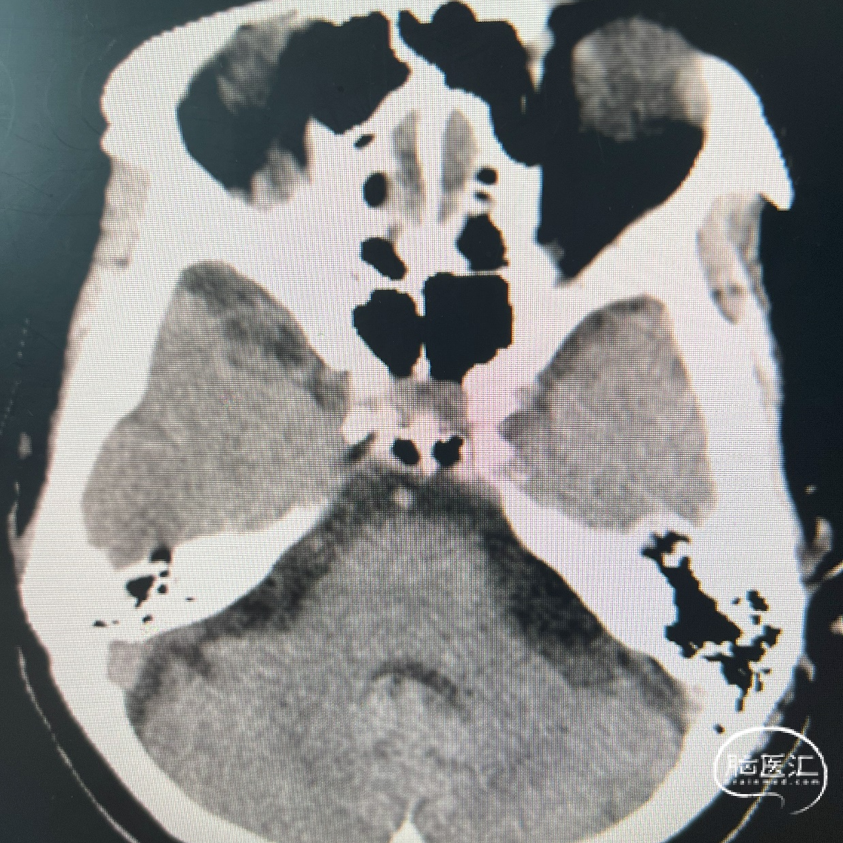

影像学表现:

1、主动脉弓及其他弓上血管,III型弓,弓上血管迂曲,血管通畅。

2、颈内动脉系统:

右侧颈总动脉及颈内动脉血管通畅,远端右侧大脑中动脉血流通畅,可见同侧及对侧大脑前动脉显影。

左侧颈总动脉及颈内动脉血流通畅,后交通开放,可见同侧大脑后动脉显影,大脑前动脉血流通畅。

3、椎基底动脉系统:

右侧椎动脉优势型。

左侧椎动脉血管纤细,远端可见基底动脉浅淡显影。

右侧椎动脉优势型,远端汇入基底动脉。

基底动脉中段重度狭窄,狭窄率约80%,双侧大脑后动脉可见显影。